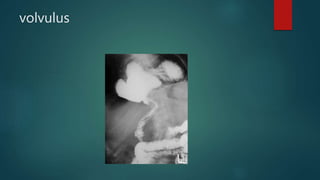

volvulus